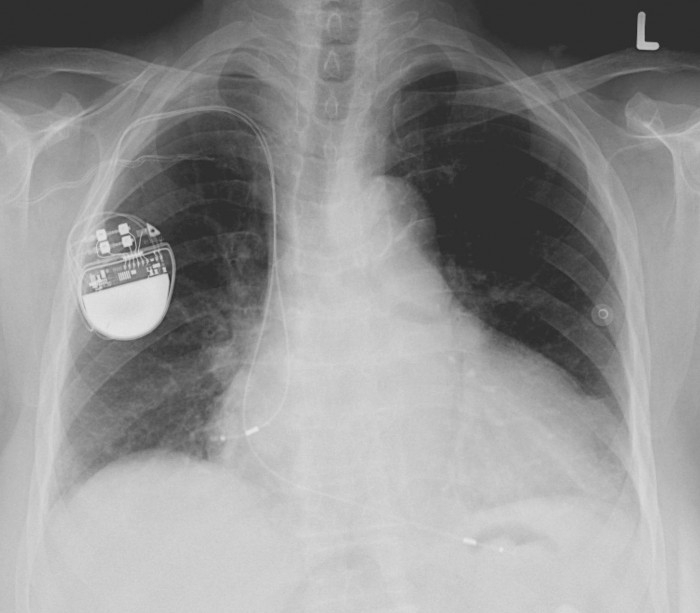

据外媒报道,虽然这种情况并不经常发生,但仍有电磁场会影响到心脏植入物如心脏起搏器性能的可能性。不过,对接受者来说幸运的是,一项新的研究表明,电动汽车产生的电磁辐射不会带来这样的危险。这项由慕尼黑工业大学的科学家跟德国心血管研究中心及新西兰惠灵顿医院的研究人员共同进行的研究招募了108名志愿者。

其中83%为男性,并且他们所有人都植入了电子设备(CIEDs),换言之,他们都曾通过手术在体内安装了起搏器和除颤器。